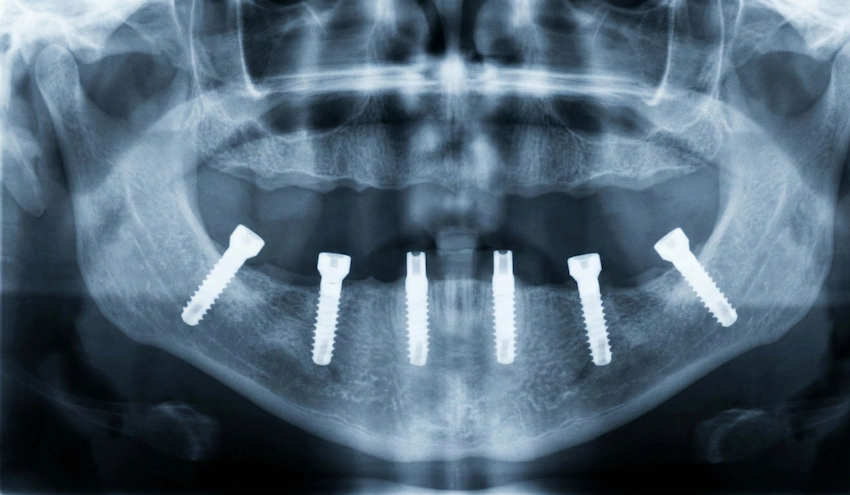

All-on-6 hambaimplantaadi ravi on meditsiiniliselt keeruline kogu suuga taastamise protseduur, mis põhineb tugevalt täppistehnikal, operatsioonipõhisel täpsusel ja pikaajalisel proteesiplaneerimisel. Euroopas erinevad hinnad selle ravi puhul suurel määral, kuna tervishoiusüsteemid, kliinilised tegevuskulud ja implantaatide töövood erinevad riigiti märkimisväärselt. Patsiendi jaoks tuleb tegelikku maksumust hinnata koos operatsiooniriskide, implantaatide püsimis- ja pikaajalise suuhügieeni ning funktsionaalsusega.

Erinevad meditsiinilised ja tehnilised tegurid määravad All-on-6 hammaste implantaatide hinna. Sellised tegurid nagu implantaatbrändi valik, luutihedus, kas luu siirdamist on vaja, ja proteesiraami tüüp mõjutavad lõplikku maksumust. Klinika, millel on oma laborid ja digitaalsed CAD/CAM-süsteemid, suudab vähendada tellimusväliseid kulusid ning suurendada proteeside täpsust.

Muud kaasnevad kulud hõlmavad anesteesia meetodeid, postoperatiivseid ravimeid ja pikaajalist hooldust. Kogenud spetsialistide, nagu Professor Doctor Coşkun Yıldız, juhendamisel tehakse implantatsioonid vastavalt tõenduspõhisele kirurgilisele protokollile, mida toetab kontuurkiirte tehnoloogia (CBCT), steriilsed operatsiooniruumid ja kontrollitud paranemisinstrumendid. Need meditsiinistandardid selgitavad, miks mõned riigid suudavad pakkuda madalamaid hindu, ilma et ohustataks patsiendi ohutust.